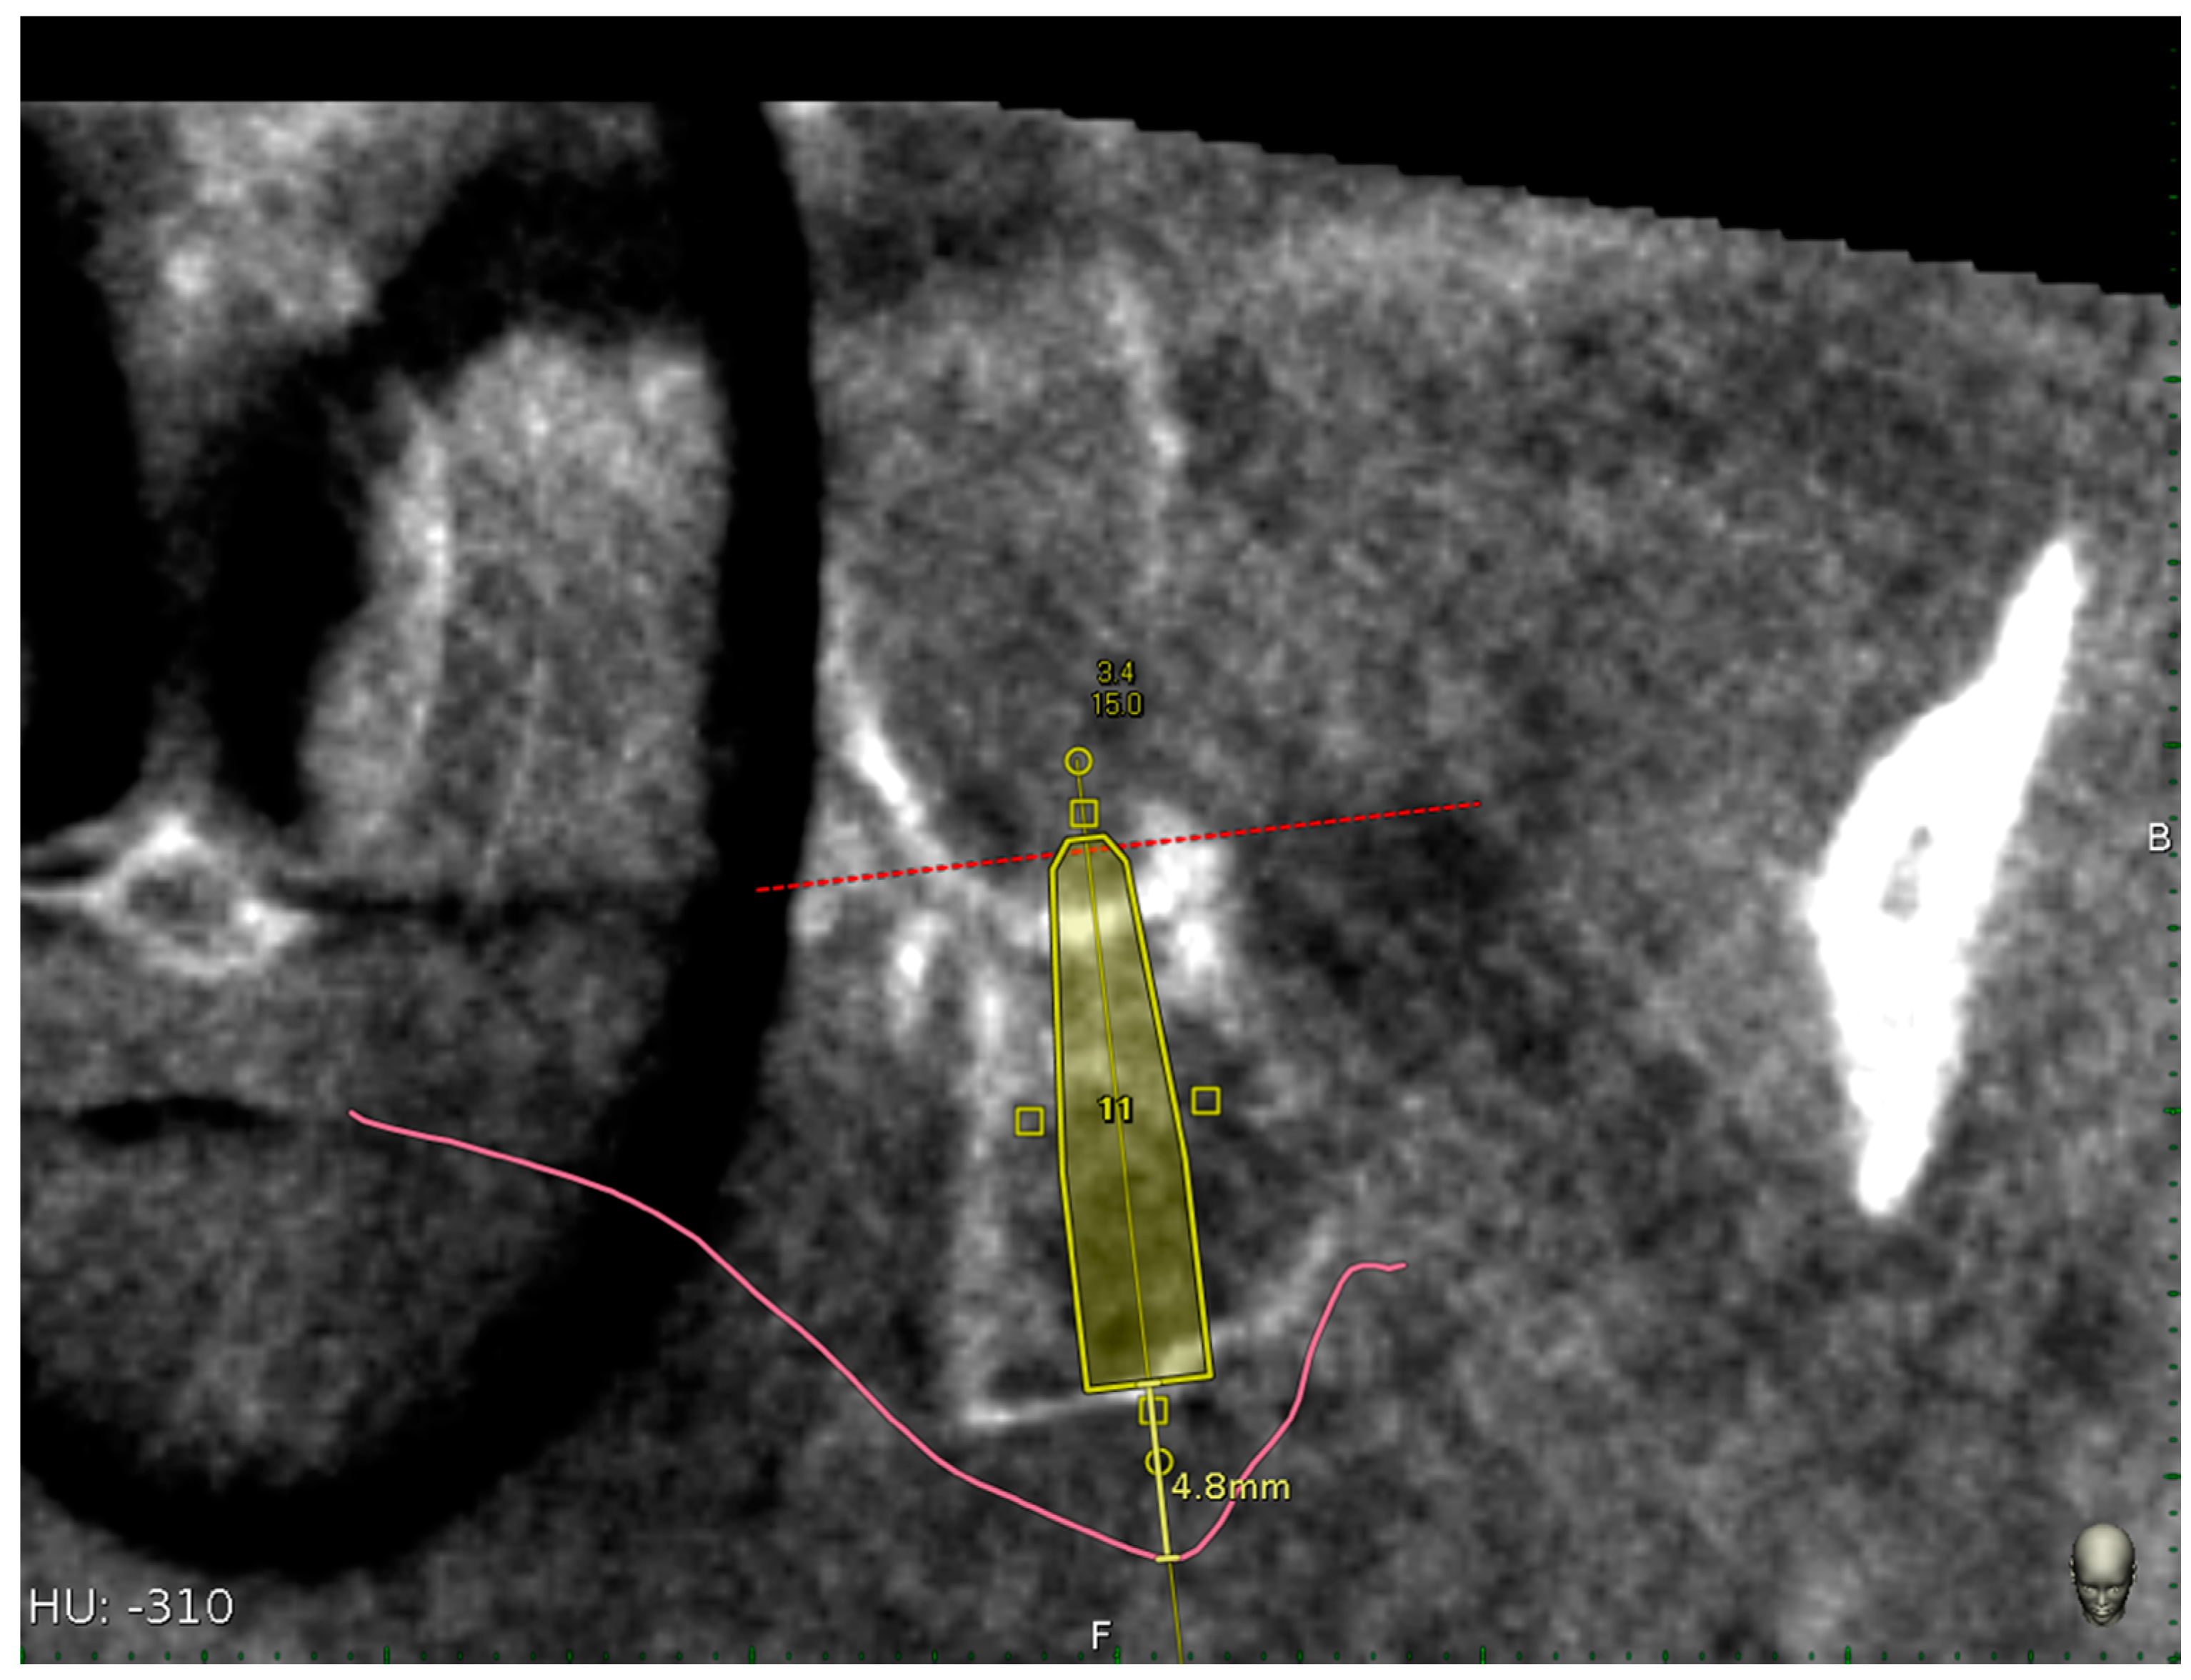

Implant survival rate, implant length, and mucosa thickness above the planned pterygoid implants were also reported (Figure 10).

Figure 10.

Mucosa thickness linear measurement using the implant centric view of the CBCT.

The mucosa thickness was calculated as linear measurement above each planned pterygoid implants by means of implant centric CBCT view.